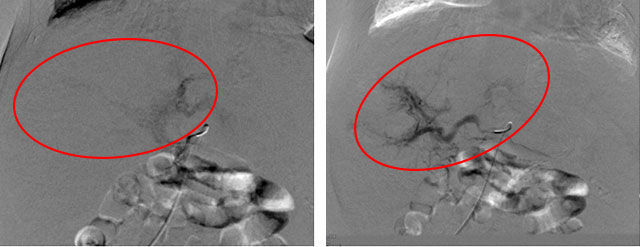

一边积极维持血流动力学稳定,一边积极跟家长沟通病情,并做好术前准备。次日张靖主任主导手术。术中见肝脏多发血管瘤及多发肝动静脉瘘形成,术中给予肝动脉栓塞,再次造影显示动静脉瘘明显减少,手术过程非常顺利。

手术后的造影